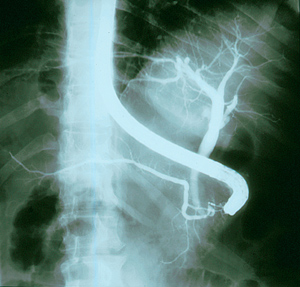

Eνδοσκοπική τοποθέτηση μεταλλικής αυτοδιατεινόμενης ενδοπρόθεσης στο χοληδόχο

πόρο, σε αποφρακτικό ίκτερο

από νεόπλασμα. Α. Ενδοπρόθεση, Β. Άποψη από το δωδεκαδάκτυλο, Γ. Ενδοπρόθεση

στο χοληδόχο πόρο.